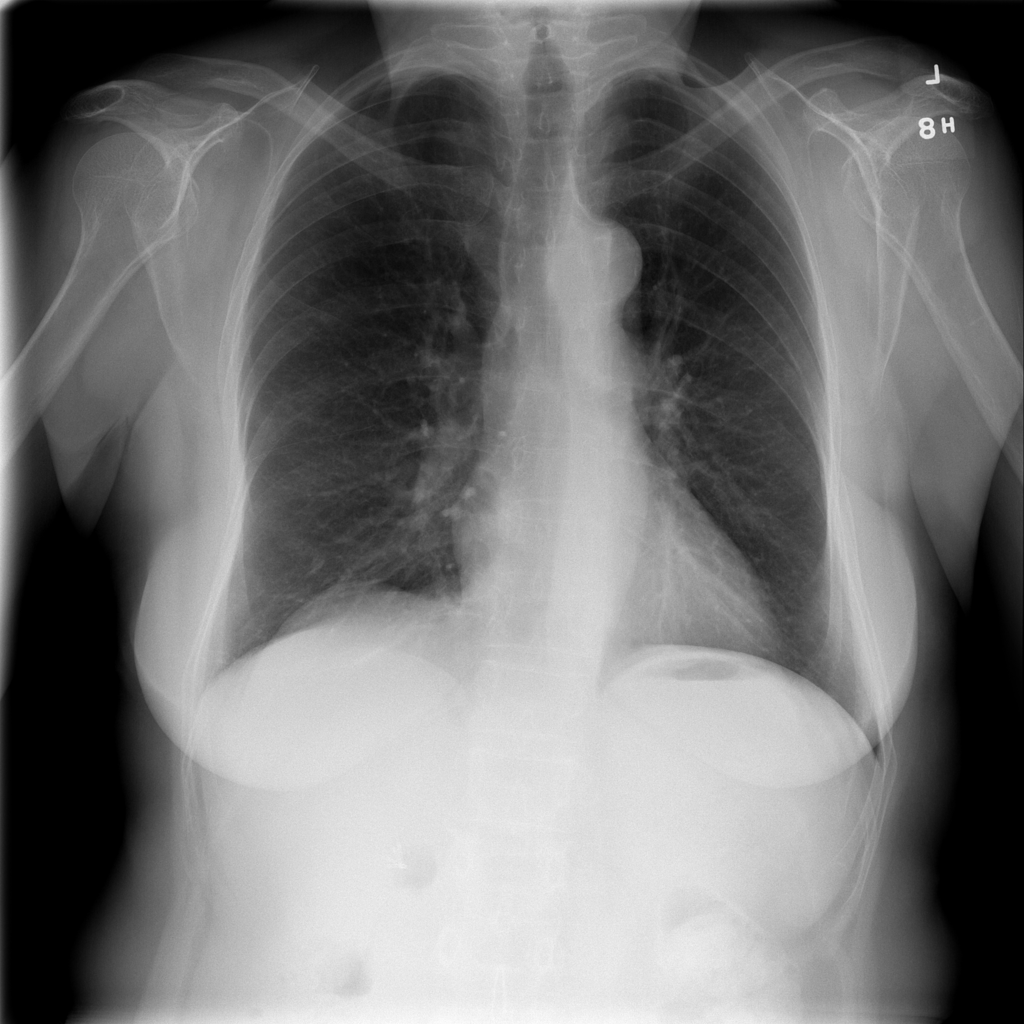

PAT-C048 · IMG-000Hernia

PAT-C048 · IMG-000

PA